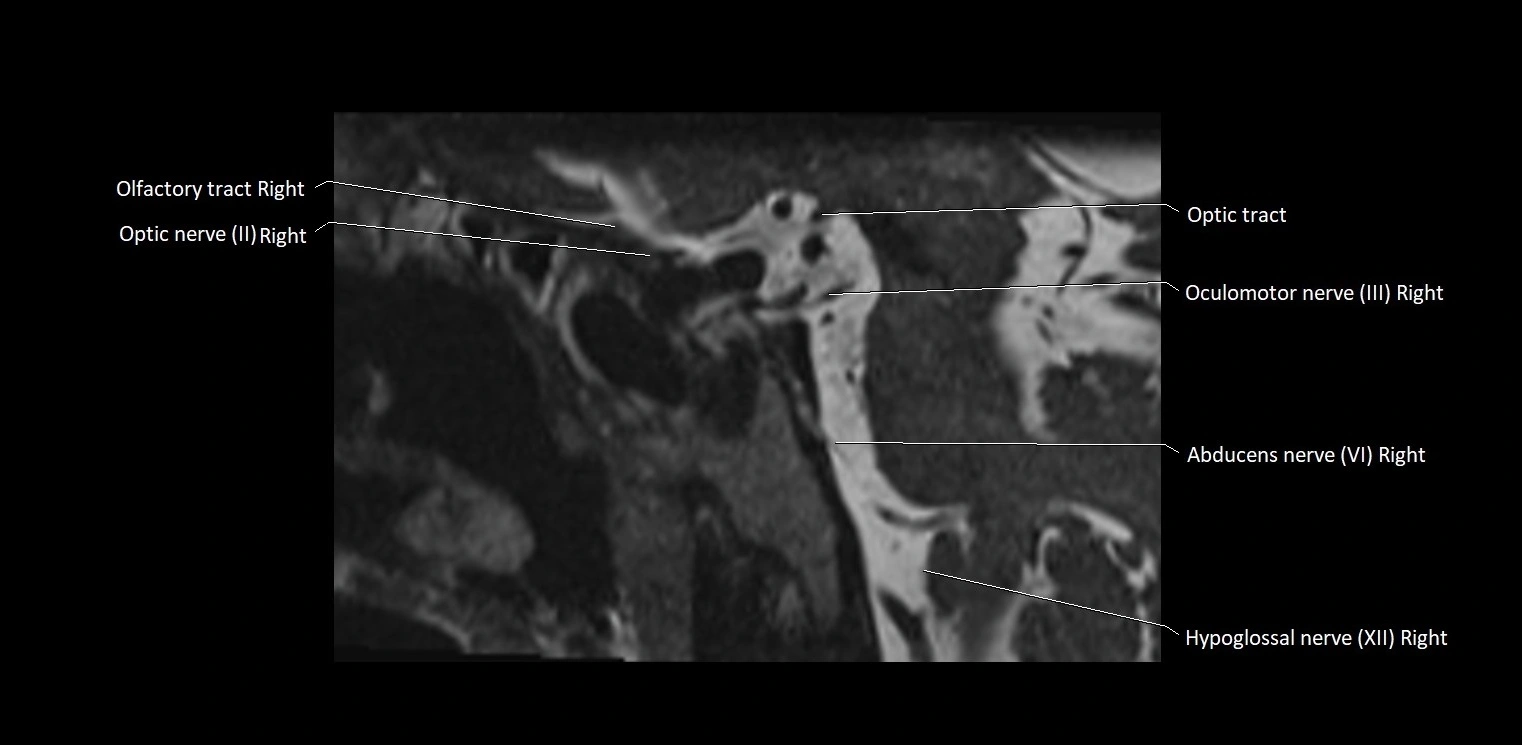

MRI Appearance

• The abducens nerve is a small, thin, linear structure

• Best visualized on high-resolution T2-weighted 3D MRI sequences (e.g., FIESTA or CISS)

• Seen as a hypointense (dark) line running from the brainstem at the pontomedullary junction, traversing the prepontine cistern, and entering Dorello’s canal under the petrosphenoidal ligament, then into the cavernous sinus, and finally the orbit

• May be challenging to visualize in standard MRI due to its small size

• Pathology may be inferred by absence, displacement, or enhancement of the nerve

MRI images

image